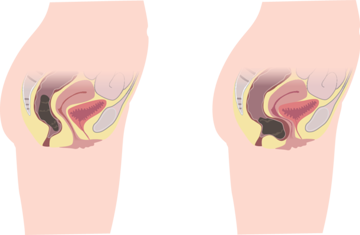

Prolaps bedeutet "aus dem Platz fallen". Ein Beckenorganprolaps (BOP) tritt auf, wenn die Scheidenwände, die Gebärmutter oder beides ihre normale Unterstützung verlieren und verrutschen. Andere nahe gelegene Beckenorgane, wie die Blase oder der Darm, können betroffen sein und ebenfalls aus ihrer normalen Position im Körper "vorfallen". Die Zystozele ist die häufigste Art von BOP.

Eine Rektozele ist eine Ausbuchtung in der vorderen oder hinteren Rektumwand, in der sich Stuhl sammeln kann, was zu einer unvollständigen Entleerung führt. In diesem Artikel erfahren Sie mehr über diese häufige Erkrankung.